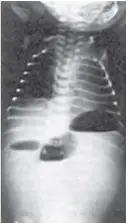

新生兒出生 1天後開始出現嘔吐症狀,嘔吐物含膽汁。身體診察發現腹部平坦,腹部 X 光片(如附圖)顯示中腹有 3團腸氣而其他部位無腸氣出現。下列何者為最可能之診斷?

新生兒腸阻塞的X光表現與梗阻部位高度相關:梗阻越高(近端),可見氣體囊越少。

- 單泡(single bubble)提示胃幽門區阻塞,如pyloric atresia或hypertrophic pyloric stenosis,且嘔吐物多為非膽汁性

- 雙泡(double bubble)為胃與十二指腸第一二部氣體充盈,遠端無氣,提示duodenal atresia或高位十二指腸梗阻(pubmed.ncbi.nlm.nih.gov)

- 三泡(triple bubble)即胃、十二指腸與近端空腸各呈一氣泡,為proximal jejunal atresia經典影像(medcraveonline.com)

- 多泡乃指多處小腸氣體積聚,為更遠端(ileal atresia或distal small bowel obstruction)